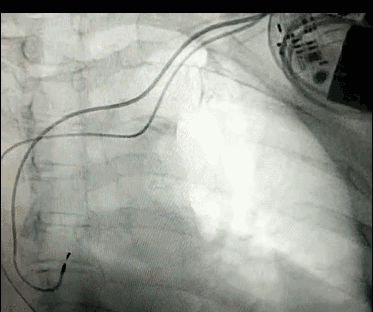

腦血管成像的“金標(biāo)準(zhǔn)”!——DSA三部曲之技術(shù)篇

DSA是將造影劑注入需要檢查的血管中,使血管顯露原形,然后通過系統(tǒng)處理,使血管顯示更加清晰,便于醫(yī)生診斷或進行手術(shù)。